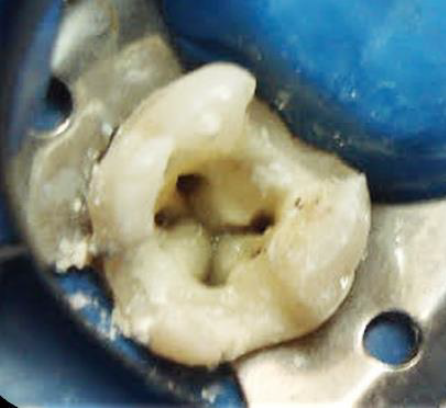

Una vez anestesiada la paciente con lidocaína al 2 % 1:10000 (ZEYCO, USA), se aisló con dique de goma y se realizó el acceso con fresa de carburo de bola #4 (SS-White, USA). Se localizaron 4 conductos con ayuda del DG16 (Hu-Friedy, USA), los conductos estaban bien definidos en el piso pulpar, uno para cada raíz; se realizó instrumentación biomecánica con sistema rotatorio ProtaperNext. (Dentsply Maillefer, Switzerland) e irrigación constante y abudante con Hipoclorito de Sodio al 5.25 %. (Figura 2)